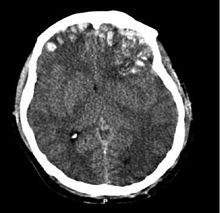

Contusión Mental . Tipo de daño cerebral adquirido, es un trauma en el tejido cerebral. Al igual que los moretones en otros tejidos, una contusión cerebral puede estar asociada con microhemorragias múltiples, pequeños vasos sanguíneos con fugas en el tejido cerebral.

- Hemorragias petequiales dispersas.

- Con frecuencia se asocian a la contusión cerebral, derrames extraencefálicos (extra o subdurales) y hemorragias primaria o secundarias que se asientan en el tronco cerebral y que se deben a hernias del uncus, originándose el edema cerebral y la hipertensión endocraneal, (esto se manifiesta a través de hipertermia de 39 – 400 C, HTA y obstrucción broncopulmonar causante de la hipoxia, trastornos vegetativos y muerte.